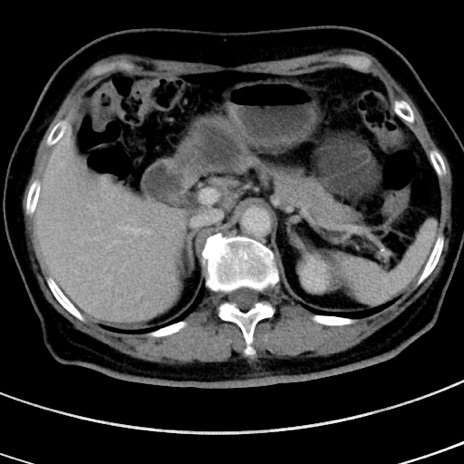

症例9(横断像)

【症例】 60歳代女性

【主訴】むかつき、みぞおちの痛み

【現病歴】3日前よりむかつきがあり、食事がとれない。

【既往歴】糖尿病

【身体所見】発熱なし、心窩部圧痛軽度あるも、腹膜刺激症状なし。

【データ】WBC 7400、CRP 1.92